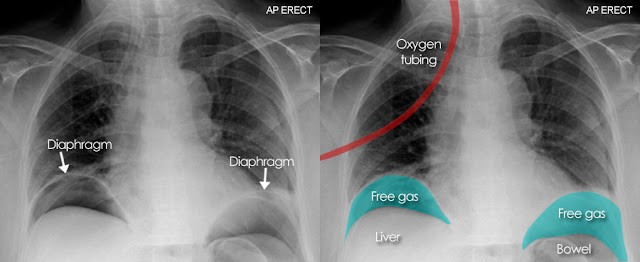

Plain radiography

An upright abdominal radiograph is often obtained in emergency settings to evaluate other causes of acute abdominal pain, such as perforated hollow viscus or bowel obstruction, but it is not useful for diagnosing appendicitis.

Figure 2. Perforated hollow viscus on upright chest radiograph: subdiaphragmatic free air crescent